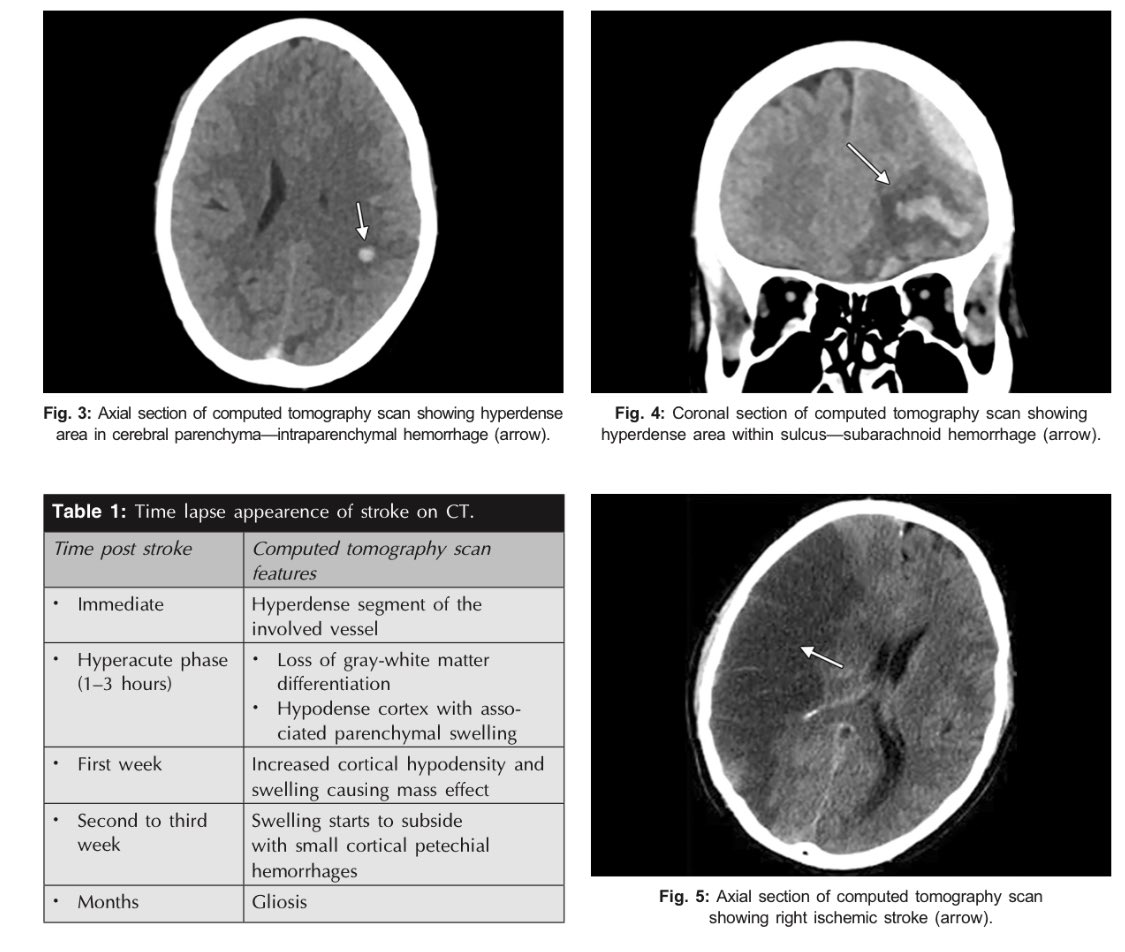

#neurology #ctscan_protocol

-Clinical and radiological features of the stroke syndromes.

-Comparison between different intracranial haemorrhages.

-CT Stroke protocol.

-Time lapse appearence of stroke on CT.